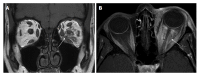

Orbital inflammatory disease (OID) represents a collection of inflammatory conditions affecting the orbit. OID is a diagnosis of exclusion, with the differential diagnosis including infection, systemic inflammatory conditions, and neoplasms, among other conditions. Inflammatory conditions in OID include dacryoadenitis, myositis, cellulitis, optic perineuritis, periscleritis, orbital apicitis, and a focal mass. Sclerosing orbital inflammation is a rare condition with a chronic, indolent course involving dense fibrosis and lymphocytic infiltrate. Previously thought to be along the spectrum of OID, it is now considered a distinct pathologic entity. Imaging plays an important role in elucidating any underlying etiology behind orbital inflammation and is critical for ruling out other conditions prior to a definitive diagnosis of OID. In this review, we will explore the common sites of involvement by OID and discuss differential diagnosis by site and key imaging findings for each condition.